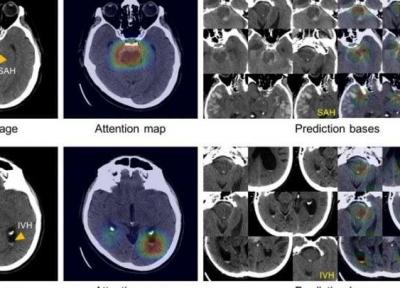

تشخیص خونریزی مغزی به یاری هوش مصنوعی

نرم افزار می تواند از روی تصاویر، لکه هایی را که سرطان زا به نظر می رسند و آسیب های چشمی ناشی از دیابت را با دقتی شبیه به انسان تشخیص دهد.